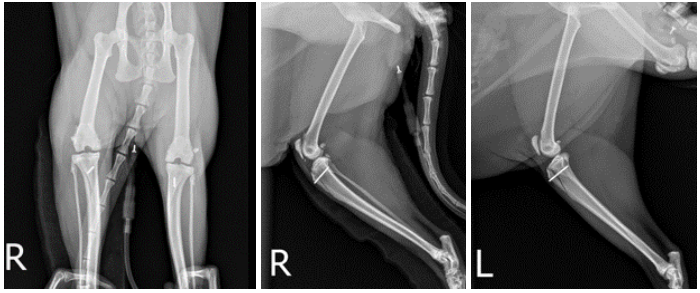

방사선 검사 : 후지 방사선 상 복배상(VD view)에서는 양측 슬개골이 활차구 내 위치하지 않고 내측으로 변위되어 있는 모습을 확인할 수 있었습니다. 또한 양쪽 무릎관절 전반에 걸쳐 골극(Osteophyte) 형성, 관절 내 삼출액 등 퇴행성 관절염 소견이 확인되었습니다. ▼

수술 직후 방사선 검사 상에서도 슬개골이 고랑 내에 잘 위치하고 있으며, 골편을 고정시키기 위한 핀도 잘 삽입되어있는 모습을 확인할 수 있었습니다.